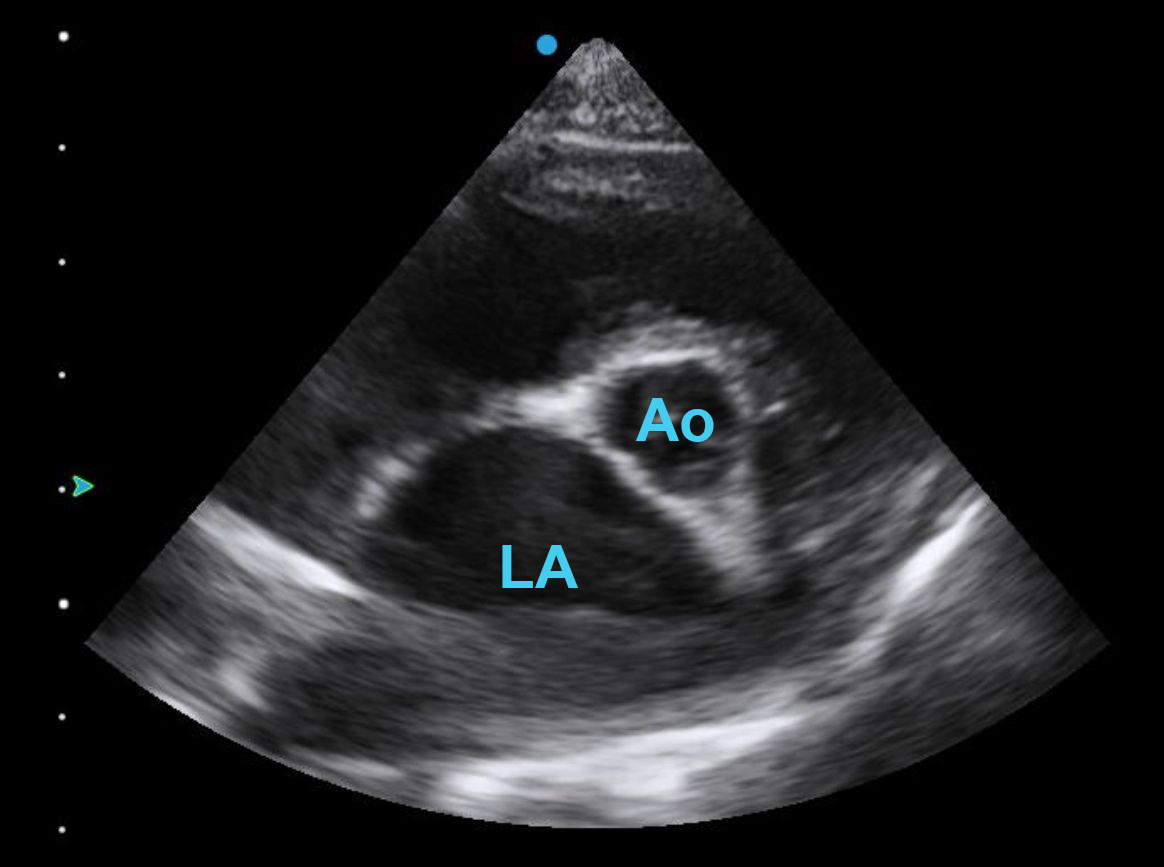

A very popular measurement in veterinary echo is the LA:Ao ratio (left atrial to aortic ratio), taken from the right parasternal short axis. This is one of the most difficult views in echocardiography, as it can be easy to under- or over-rotate your image, or cut the base of the heart obliquely so that the aortic valve leaflets look unequal in size.

The aim is to have the aortic valve appear as a circle – if you can see a hint of the outflow track to the left of your image, you have under rotated, and if you see it appearing on the right, you have rotated too far. The above example is typical of the type of image routinely achievable. Textbook-style clarity with all three leaflets perfectly seen may not be possible in every patient in real life.

An LA:Ao ratio >1.5 is considered dilated in dogs, with a little more tolerance given to cats, but even without measuring, it is easy to see from this view that this left atrium is dilated. Also notice how the interatrial septum, seen on the left border (in this view) of the LA, bows into the right side of the heart. This is commonly seen when the left atrium is dilated due to excessive volume or pressure.